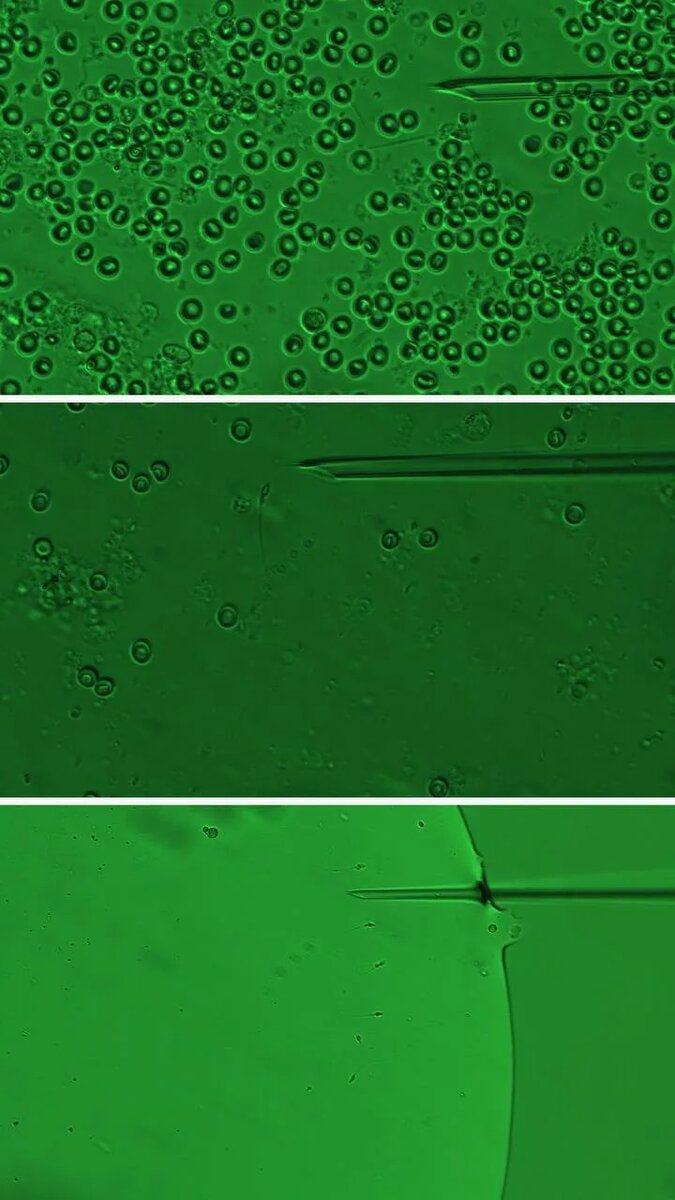

— 6 часов работы за микроскопом.

— Фрагмент за фрагментом.

— обнаружено 6 сперматозоидов

— Каждый находится вручную.

— Каждый сохраняется.